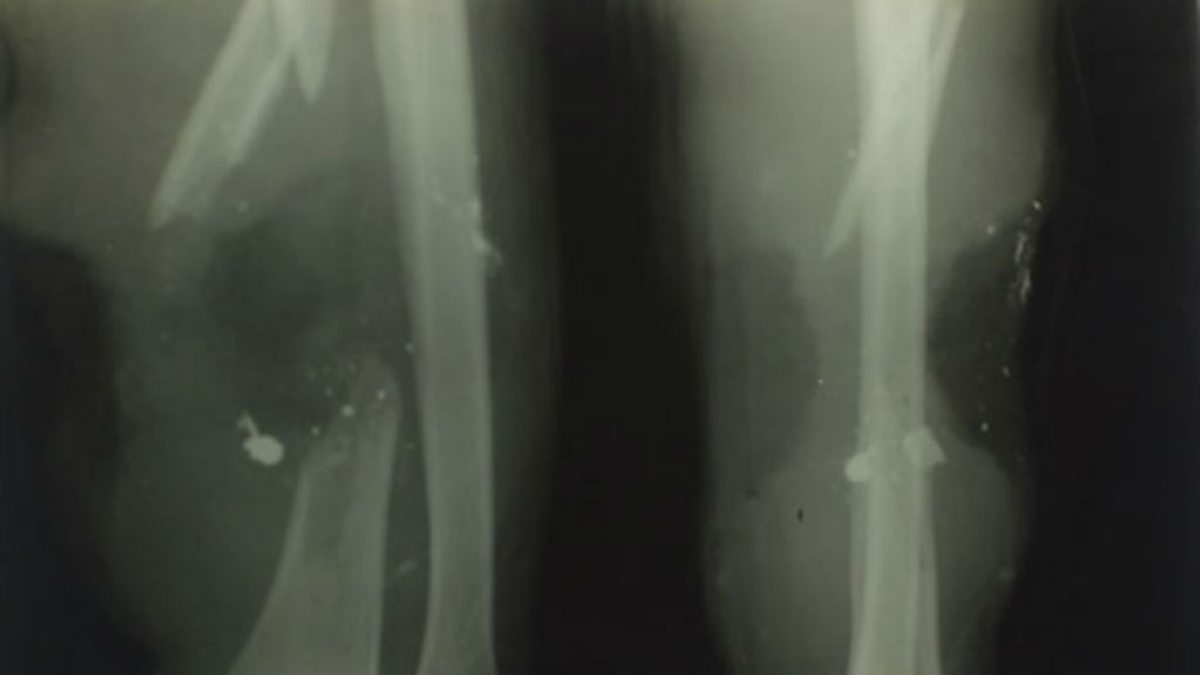

Private Hori Woolgan Jarvis of the 11th Royal West Kent Regiment had his arm shattered by a German sniper’s bullet on 14 June 1917. Many wounded soldiers with such severe injuries and shrapnel would have lost limbs through amputation but Private Jarvis was fortunate to be treated at Tunbridge Wells General Hospital.

Here he was treated by the most cutting edge X-ray department outside London. Not only did X-ray make it possible for him to have a bone graft but the success of the treatment enabled him to return to his pre-war occupation as a baker and pastry chef.

Image: Private Hori Jarvis’ X-ray, courtesy of Liz Douglas from Tunbridge Wells Museum